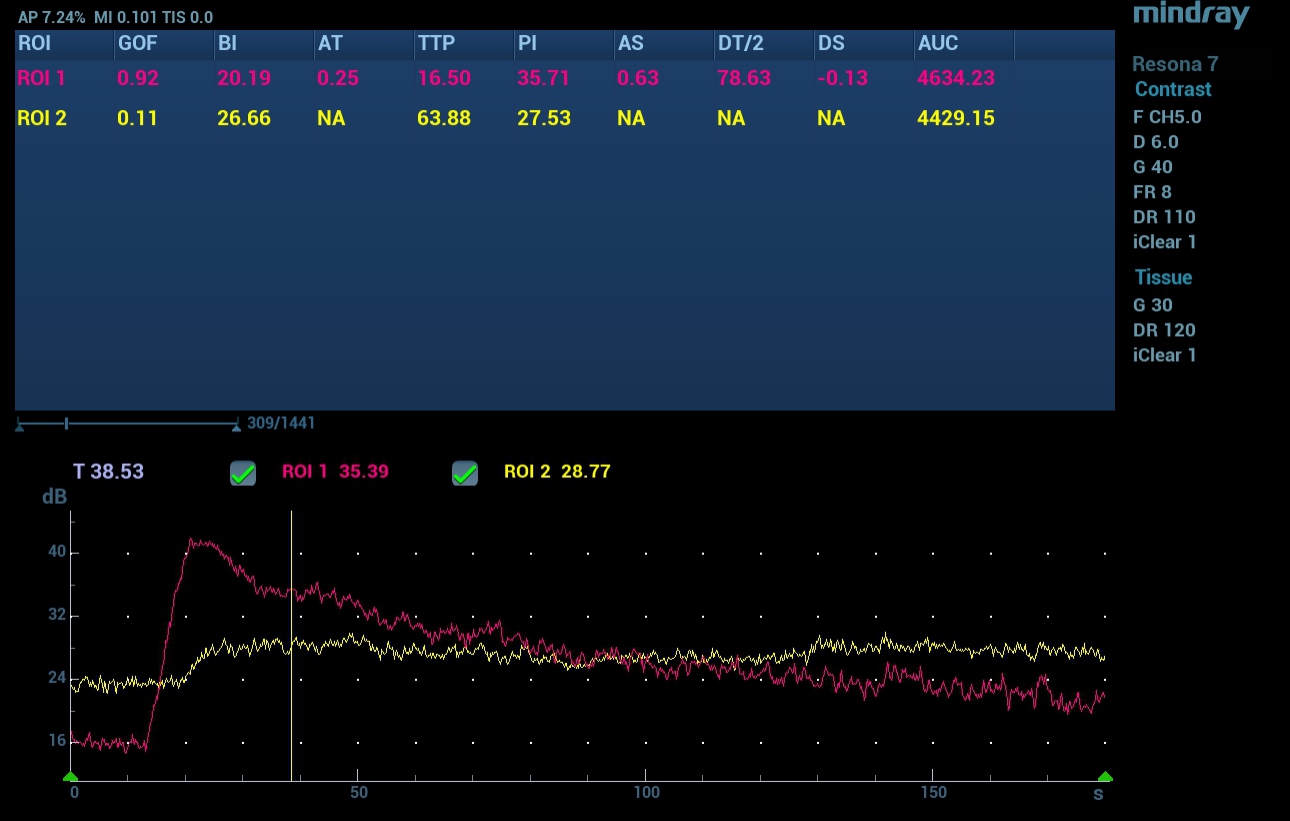

Contrast Imaging Quantification Analysis

The timeŌĆōintensity curve of the focal lesion was characterized by a rapid rise and subsequent rapid fall. The main quantitative indicators were TTP 16.5 sec., PI 35.7 dB, DT/2 78.6 sec., AUC 4634.2 dB/sec. For the intact peripheral zone, the timeŌĆōintensity curve was characterized by a smooth rise and subsequent plateau phase, TTP was 63.9 seconds, PI 27.5 dB, AUC 4429.2 dB/sec. The DT/2 parameter was not determined (Fig. 5).

Classical ultrasound signs of prostate cancer are considered to be hypoechoic, hypervascular formation in the peripheral zone with a fuzzy contour [1]. These signs are characterized by low specificity, since similar changes can occur with various benign changes [2]. In this regard, multiparametric ultrasound is necessary to provide additional diagnostic information. Strain elastography can provide a map of the tissue stiffness in a given region of interest. While malignant lesions tend to be stiffer than normal tissue, this is not always so, as seen in this particular case where strain ratios did not indicate significant change in stiffness between the focal lesion and the surrounding intact tissue. CEUS can provide more detail regarding tissue vascularity. In this case, CEUS examination confirmed pathological vascularization within the focal lesion seen on B mode imaging, not just by qualitative signs, but also by quantitative parameters.